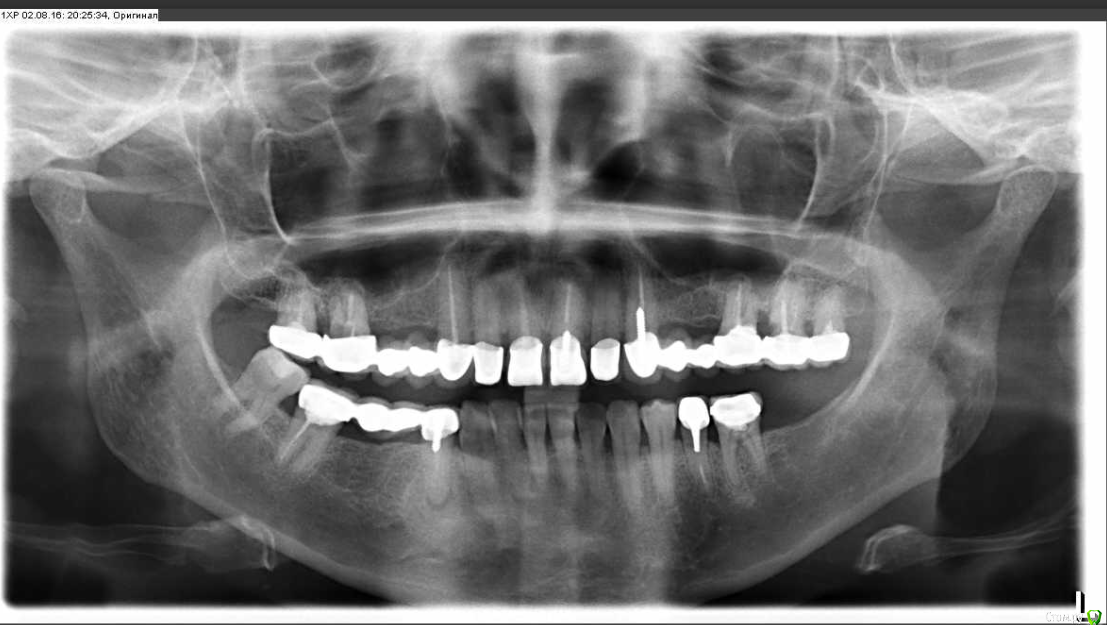

chervoncevdaniil Опубликовано 30 июля, 2016 Поделиться Опубликовано 30 июля, 2016 Выложите панорамный снимок,если есть Ссылка на комментарий

krokomot Опубликовано 30 июля, 2016 Поделиться Опубликовано 30 июля, 2016 Решите для начала проблемы с жевательными зубами, а потом передними, в таком состоянии я бы не стал сейчас делать пластику десны. Ссылка на комментарий

DmitrySH Опубликовано 30 июля, 2016 Поделиться Опубликовано 30 июля, 2016 фактически все жевательные зубы, где ранее были удалены нервы, требуют лечения Ссылка на комментарий

Ленусик333 Опубликовано 31 июля, 2016 Автор Поделиться Опубликовано 31 июля, 2016 О, я не написала, панорамный снимок сделан ДО лечения, сейчас все зубы пролечены. Ссылка на комментарий